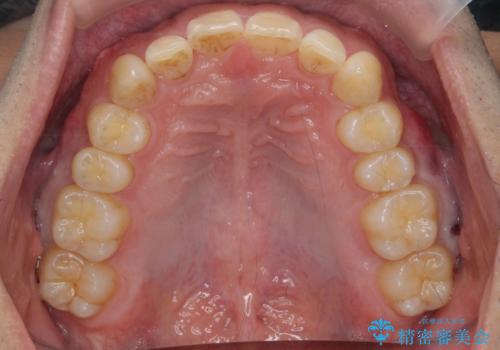

出っ歯を治したい 深いかみあわせ インビザラインで治療

上顎は歯を抜かずに、奥歯を後ろに下げる治療を行っています。

歯を抜かずに奥歯を後ろに動かすために、矯正用のミニスクリューを使用しています。

また、過蓋咬合(深いかみ合わせ)で食いしばりがきつく、歯の移動には大変時間がかかりました。